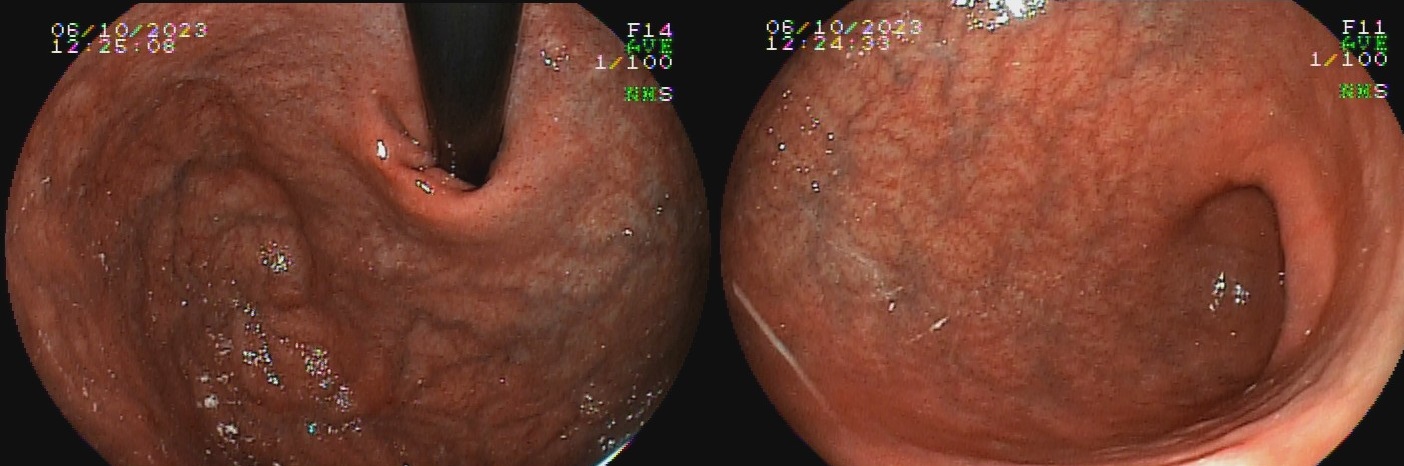

O termo gastrite crônica atrófica refere-se à atrofia da mucosa gástrica causada pelo H. pylori. Inicialmente, a mucosa sofre agressão por neutrófilos, e mais tardiamente, por monócitos. Com o tempo, essa agressão reduz a população de glândulas, tornando o relevo reduzido e a mucosa mais pálida. A diminuição da espessura da camada mucosa torna os vasos da submucosa mais evidentes ao exame endoscópico. Segundo a evolução descrita por Kimura-Takemoto, essa patologia tem início no antro e incisura angular (C1),  e progride em direção à cárdia pela pequena curvatura do corpo, e, após atingir a região mais proximal do estômago (C2 e C3), a progressão inicia abertura da região acometida, expandindo-se em direção às paredes anterior e posterior do corpo e fundo simetricamente (O1 e O2), até acometer a grande curvatura (O3).